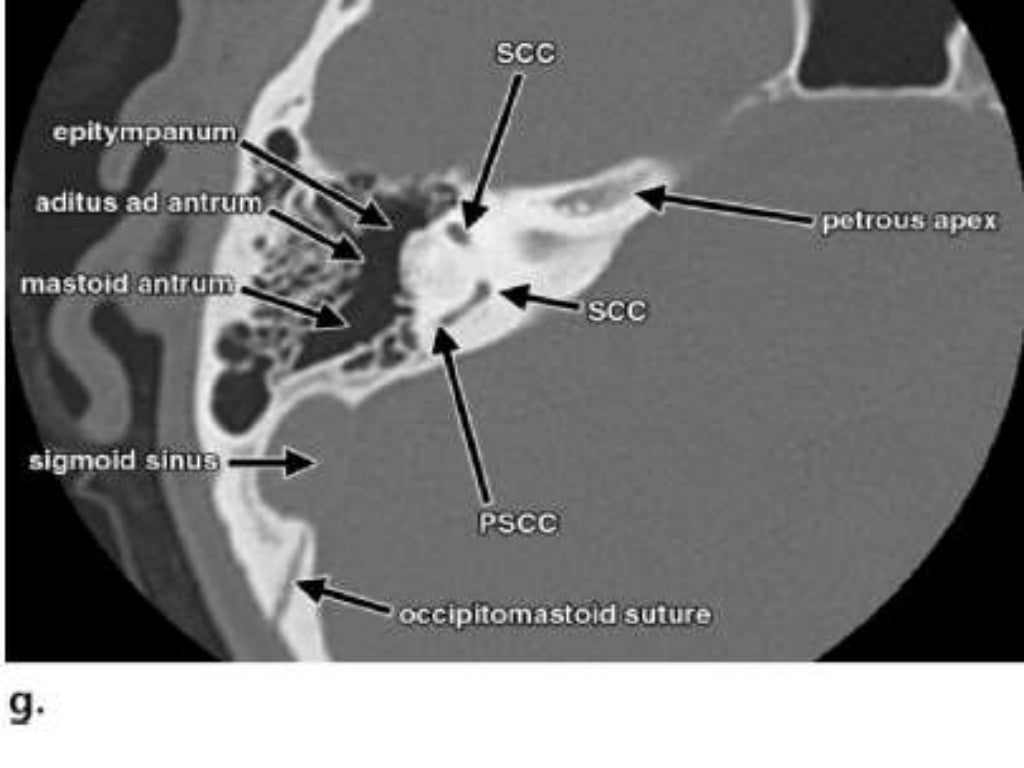

- HRCT Temporal bone anatomy

- Planes of scanning Axial 30 Degrees to anthropological base line Parallel to lateral SCC. Best displays inner & middle ear. ...

- Temporal Bone 1.Squamous 2.Petrous 3.Mastoid 4.Tympanic 5. ...

- EAR IS DIVIDED INTO 3 PARTS • EXTERNAL EAR • MIDDLE EAR • INTERNAL EAR 5 EAC Tympanic cavity Bony & membranous labyrinth

CT and MRI are primarily used for imaging of the temporal bone. We first present the standard technique and protocols most often used, then review the special considerations for both modalities. A brief overview of the roles of plain radiographs, ultrasound (US), positron emission tomography (PET), and PET/CT is given at the end of this section.

Gross anatomy. The temporal bone is divided into several main parts/portions 1-3: In addition, there are several bony projections: The temporal bone can also be divided into otologic zones:

Which otologic zone is the mastoid process?